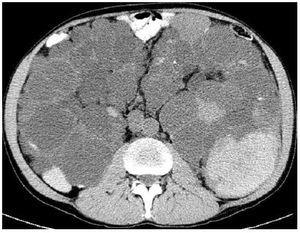

El carcinoma de células renales no es una causa frecuente de dolor en pacientes con PQRAD. La frecuencia no es superior a la de la población general, aunque puede presentarse a una edad más temprana, con frecuentes síntomas constitucionales y una proporción más elevada de tumores sarcomatoides, bilaterales, multicéntricos y metastásicos (figura 6). Frente a la presencia de una masa sólida en la ecografía o una masa con calcificaciones espiculadas en la TC o en la RM, y captación de contraste en la TC, se debe sospechar un carcinoma.

Figura 6. Tomografía computarizada de una paciente mujer de 62 años de edad.